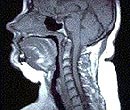

Airway

Closure During Sleep - Apneic

Apneic

Patient (Mid- Sagittal Section)

Normal

Subject (Mid - Segmental Section)

Soft

Tissue Comparison of an Apneic and a Normal